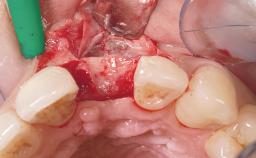

Late Placement of an Implant in a Maxillary Left Central Incisor Site

A 36-year-old female patient was referred for the replacement of the upper left central incisor (tooth 21), which had fractured. Although the tooth had been asymptomatic for many years, the crown began to loosen, at which time she presented to her dentist for an assessment. Teeth 21 and 22 had both been endodontically treated many years previously. She was a healthy individual and a non-smoker.

Soft Tissue Grafting Simultaneous

Bone Volume Deficient horizontally, requiring prior grafting